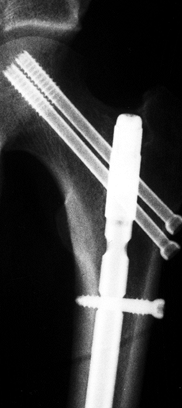

Careful examination of both hips and AP

and lateral x-rays in internal rotation showed no evidence of fracture

of the femoral neck. In follow-up, an undisplaced fracture of the left

femoral neck was found and fixed with cannulated screws.

statically locked reamed nail. At that time she was complaining of pain

in the left hip. X-rays revealed an undisplaced fracture of the left

femoral neck. This was fixed with percutaneous cannulated screw

fixation anterior to the femoral nail (Fig. 14.14).

| Figure 14.14. Left femoral neck fracture after screw fixation at 6 weeks, anteroposterior view. |